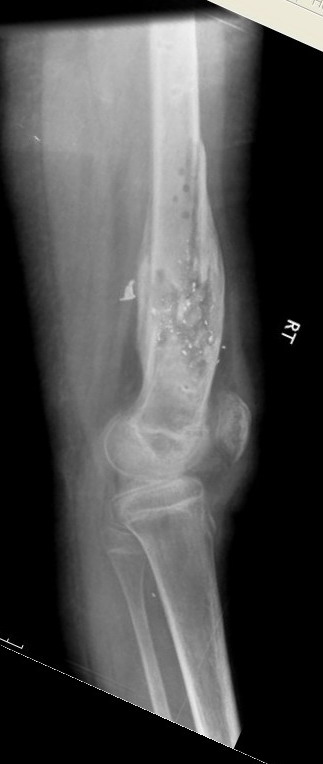

Выше приведены рентгенограммы 13-летнего подростка, страдающего от огнестрельного многооскольчатого перелома дистальной трети бедра. AO наружный фиксатор наложенный в день травмы не дал приемлемой редукции. Через три недели после перелома аппарат Илизарова был наложен без попытки одномоментной репозиции на операционном столе.

There are X-Rays of a thirteen year old boy with a comminuted distal femur fracture secondary to a gunshot wound, initially treated with an AO external fixator. The alignment was unacceptable and an Ilizarov external fixator was applied three weeks after the injury. No attempt of definitive reduction was made during the surgery.

Гексаподная приставки наложена на 10 дней и приемлемая редукция была получена.

The Hexapod set was applied for ten days and acceptable reduction was received.

По окончанию редукции Гексаподный сет был снят и дальнейшее ведение больного проходило в стандартном режиме аппарата Илизарова. Хороший анатомо-функциональный результат был получен.

When reduction was finished, the Hexapod set was removed and further management has been continued by standard Ilizarov regime. Good anatomic and functional results were achieved.